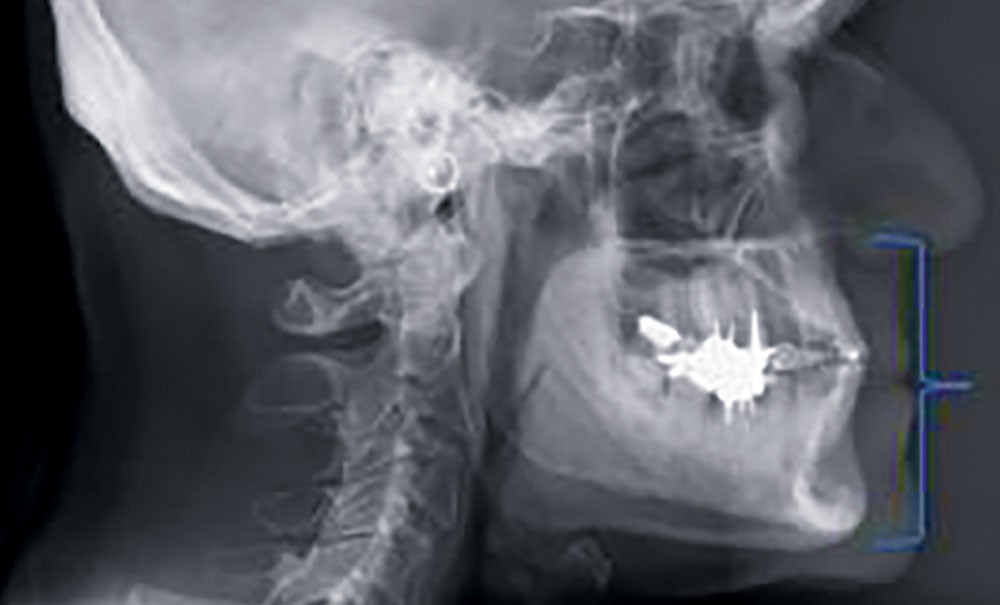

Les indicateurs esthétiques (harmonie du visage, esthétique), céphalométriques et dentaires (hauteur prothétique, relation occlusale antérieure) seront autant d’éléments évoqués pour évaluer la DVO initiale [6] et déterminer les limites de modification.